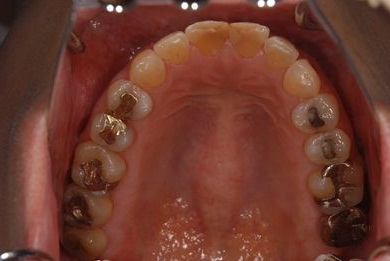

治療前

• 治療前